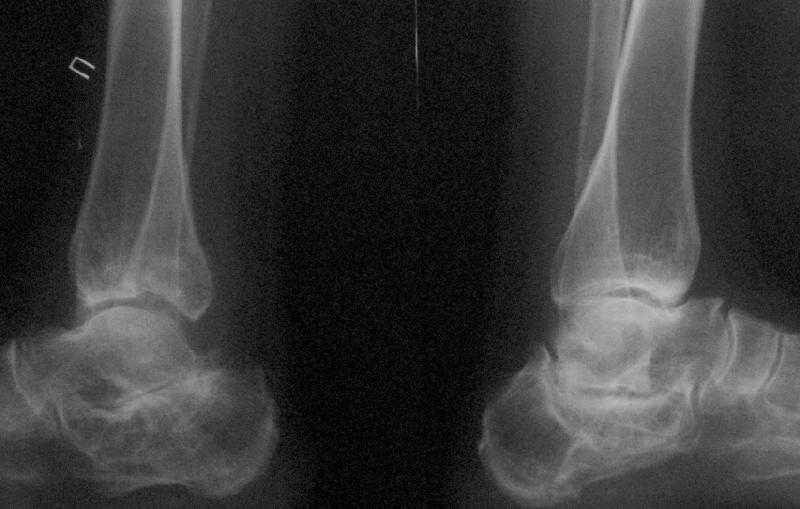

Уважаемые коллеги! Помогите определится с тактикой лечения.Оскольчатый импрессионный перелом заднего края правой большеберцовой (Пилон?) кости 5-ти недельной давности на фоне неправильно сросшихся переломов пяточных костей (травма в 1991г.), ДОА подтаранных суставов 3 ст. До последней травмы больная ходила без особых проблем и работала пекарем (работа на ногах).Суть проблемы в том, что открытая анатомическая репозиция в таком сроке представляется мне крайне травматичной, что может привести к неблагоприятному функциональному исходу.Варианты решения:1) оставить "как есть" с последующим артродезом после развития ДОА2) выполнить остеотомию и попытаться низвести основную часть суставной поверхности3) выполнить попытку анатомической репозиции из задне-латерального??? доступа.

По снимкам довольно сохранный сустав, и такой сустав желательно попытаться восстановить всеми возможными мерами.

Артродез штифтом от Синтеза - немного агрессивно, а для улучшения качества жизни вместо артродеза голеностопа можно было бы предложить артродез подтаранного сустава. Тремя 6.5 мм каннюлированными шурупами через пятку.

Подобные скиаграммы я рисовал до КТ. На картинке получается красиво, но на деле задний край не имеет единой суставной поверхности и не понятно что и на сколько низводить. Рискуем получить "+ ткань" в суставе, а это ещё хуже.